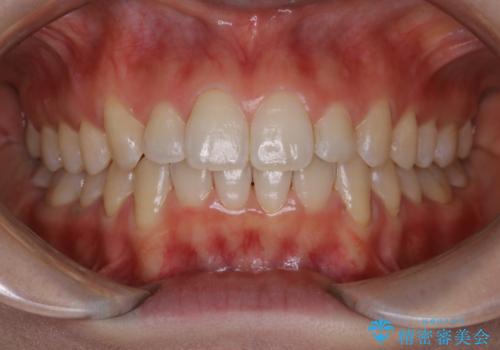

前歯の着色をPMTCできれいに

- 前歯に付着している着色がきになるとのことでした。PMTC30分コースを行いました。

PMTCとはプロフェッショナル・メカニカル・トゥース・クリーニングの略です。

専門的な機械や器具を使用して歯のクリーニングを行います。